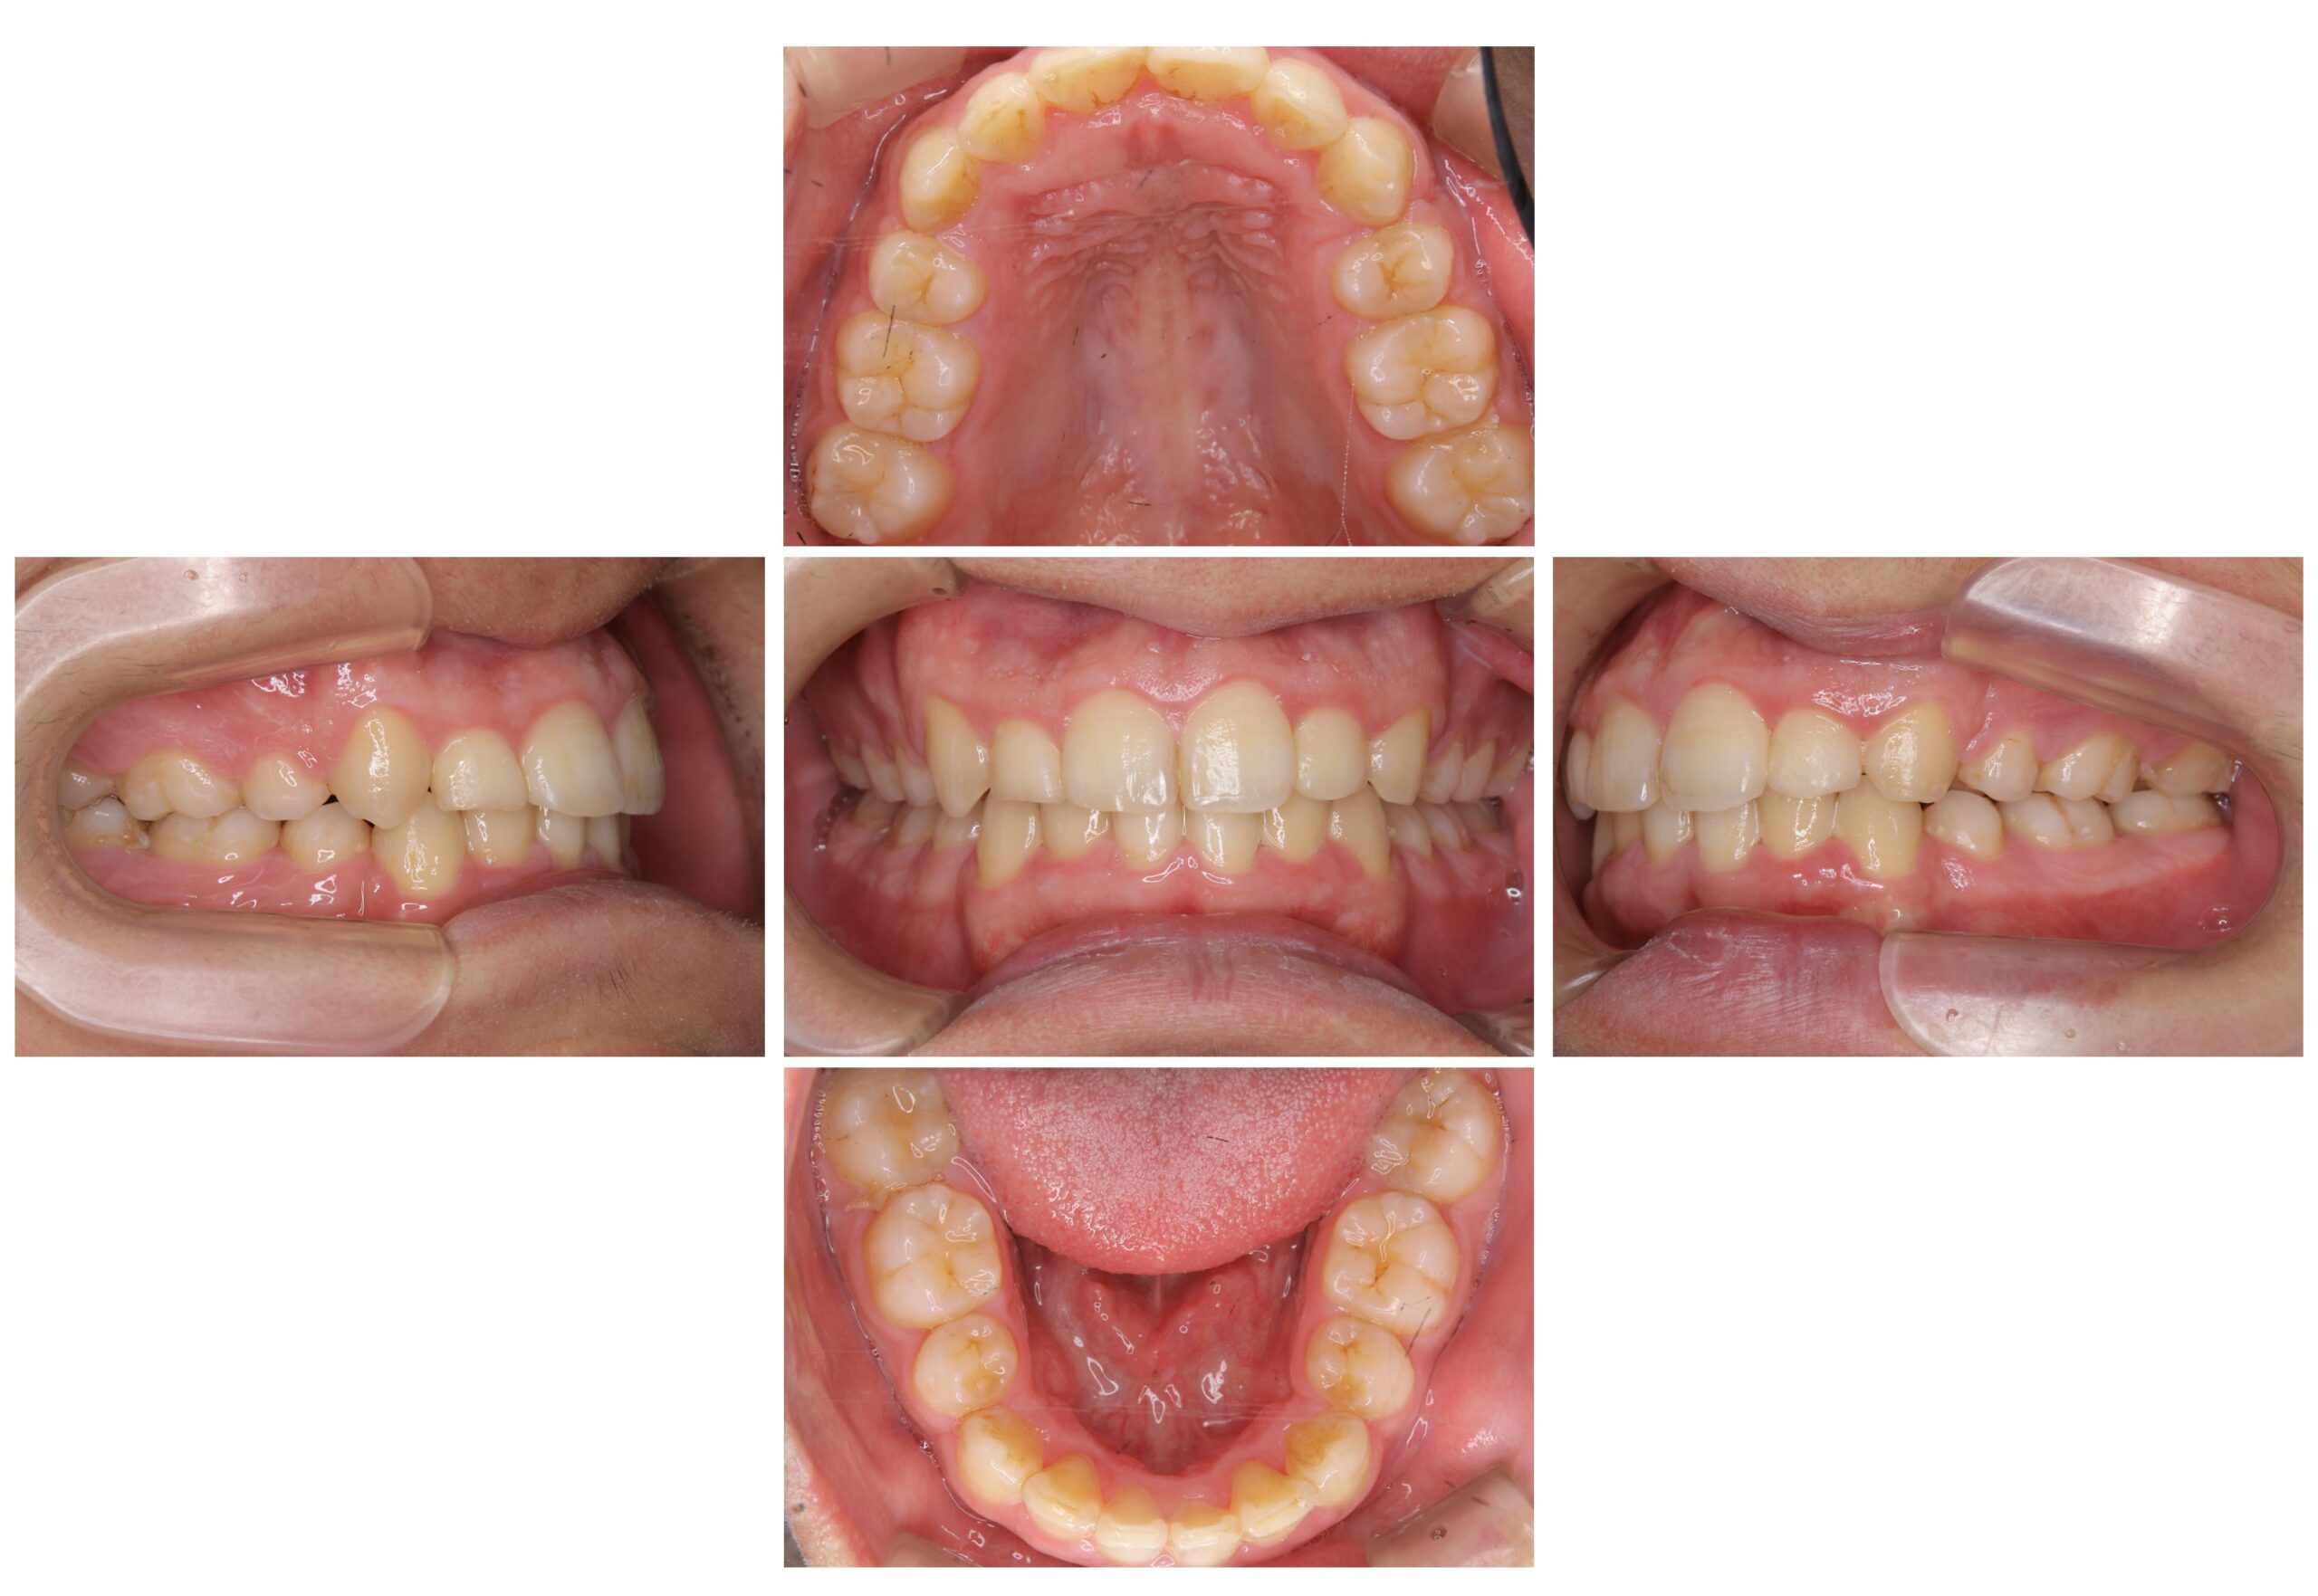

【治療に用いた主な装置】

ワイヤー矯正

・セラミック製・セルフライゲーションブラケット装置(クリッピーC)

・ロジウムコーティング・ホワイトワイヤー

治療期間・回数

1年10か月

費用

968,000円(税込) 調整料 5,500円(税込)

リスク・副作用

治療中の違和感、痛み、むし歯、歯周病、歯根吸収、歯肉退縮、歯髄壊死、顎関節症